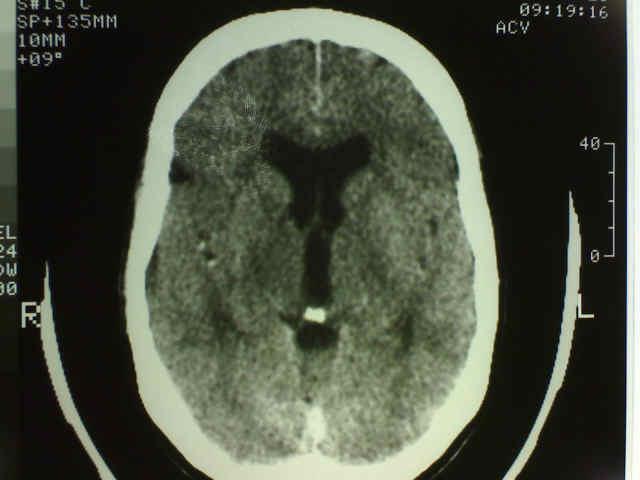

Enfermedades Degenerativas

En este grupo de patologías se encuentran trastornos de movimiento como la Enfermedad de Parkinson, enfermedades desmielinizantes como la esclerosis multiple y trastornos de la memoria como la enfermedad de Alzheimer. Son enfermedades progresivas, discapacitantes, crónicas, que necesitan tratamiento de soporte a largo plazo. La mayoría de estas enfermedades son vistas por Neurología. El rol de la neurocirugía se limita a biopsias, colocacion de neuromoduladores, manejo del dolor, etc. La figura de la izquierda muestra cierto grado de dilatacion ventricular, hallazgo frecuente en estas patologias.